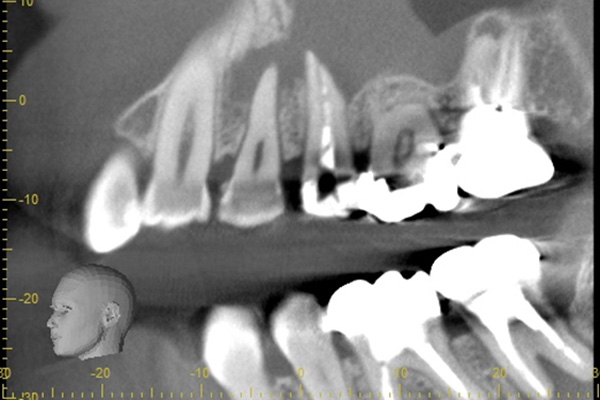

こちらは根の中の防腐剤が疎で、最近が繁殖するスペースをあたえてしまっていたため、患者様に違和感を感じさせていました。そこで、中の防腐剤を取り除き、それをCTとマイクロスコープで確認し、清掃を行い、今度は緊密に防腐剤を入れていきました。

こちらは根の治療の経験がある歯ではありませんが、歯茎が大きく腫れていらした患者様です。レントゲンを撮ってみると原因となっていそうな、2本怪しい歯がありました。過去の虫歯の経緯から後ろの歯の方が怪しいと判断し、1本だけ治療を行いました。

治療後、腫れの大きさの確認のためにCTを撮影すると、上顎洞にまでおよぶ大きな炎症があり、骨が大きくなくなっていることが確認できました。

基礎に忠実に根の中をしっかり清掃し、防腐剤を詰めて経過をみるために3ヶ月後に再度CTを撮影しました。以前とは比べ物にならないくらい、上顎洞の炎症はなくなり。上顎洞を隔てる骨の再生もできました。 またこの治療で一番良かったのは、治療しなければならない歯とそうでない歯を鑑別できたことです。手前の歯はやはり治療する必要がなかったのです。

初診終了後にCT撮影です。上顎洞と歯が連続してしまうくらい炎症が広がっています。

根の先に黒い影があり、2本ともあやしいです。

きっちり清掃を行い防腐剤をつめました。

まだ根の先端に黒い影はあるが、治癒傾向にあると判断できます。